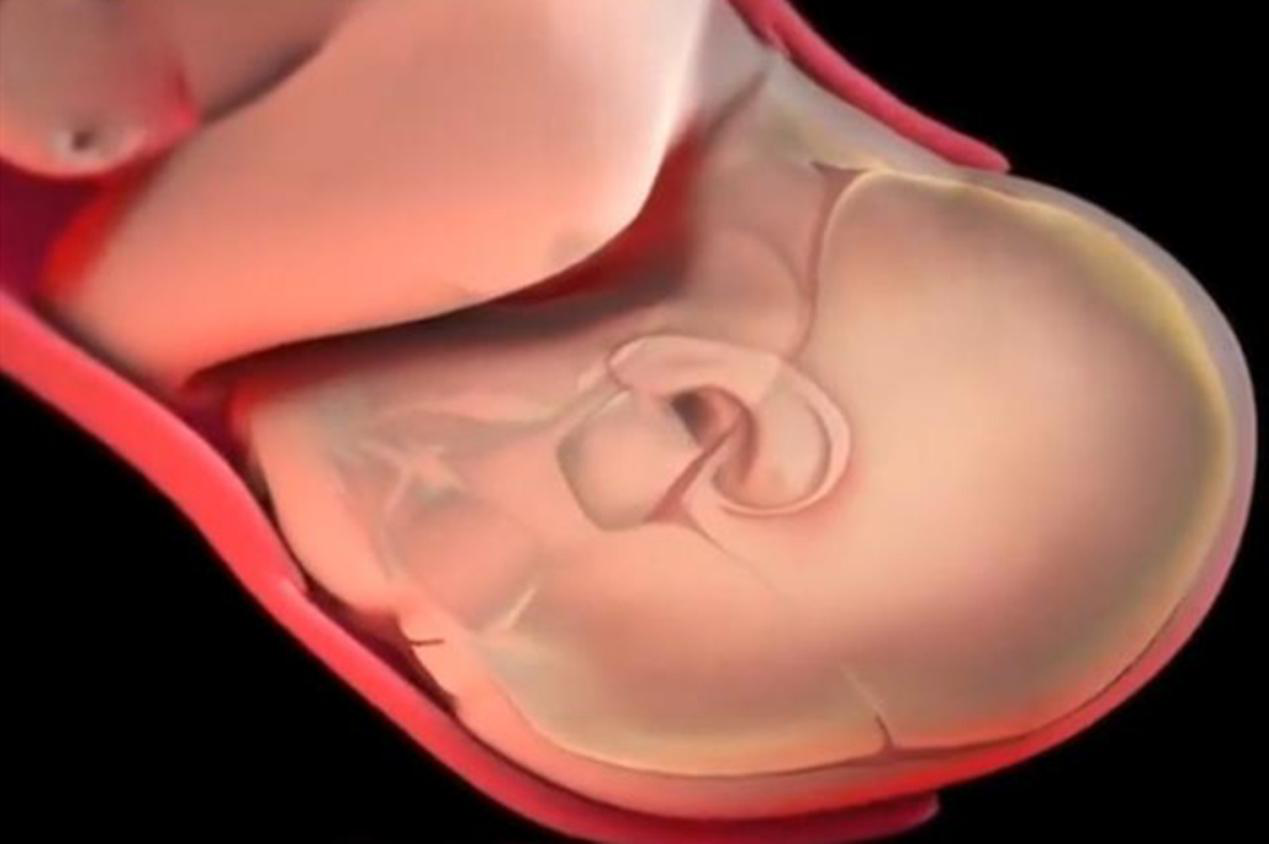

女性体内有一种叫做羊膜囊的组织,它的内部都是液体,并以此来保护胎儿的安全。而羊膜囊的破裂,也就叫做破水。

羊膜囊破裂,自然会有液体流出,流出的液体就是羊水。孕晚期一旦出现这种情况,就是产妇快要生了的一种信号。

胎儿出生时,他们的头骨会发生重叠情况,通过减小面积,来保障顺利通过产道。

看过新生儿的人都知道,好多孩子的头部看起来都不是很规则,仿佛被挤压得尖尖的。

这种情况很正常,主要是由于孩子的头骨尚未发育完全,几个月后就会调整回来了。

待宝宝的头顶出来后,医护人员会帮助做复位调整,让孩子顺利产出。

宝宝的头部彻底出来后,也算解决了一大难点,这是胎儿身体最宽的部分。

头部出来后,接着也就是肩膀了,到这里,就差不多接近分娩的尾声阶段了。

胎盘虽然会包裹着孩子,却不会和孩子的出生同步,一般都会在孩子出生的几分钟后,才会被娩出。